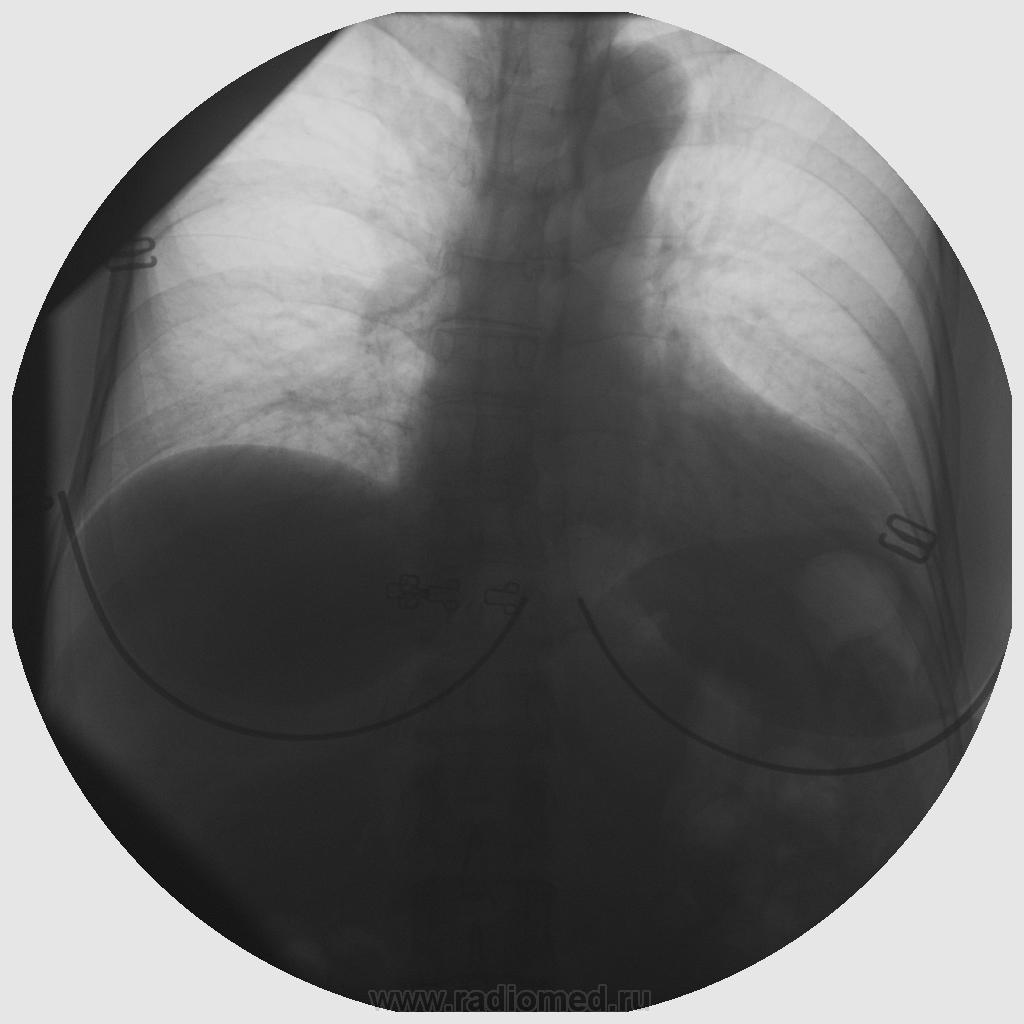

вот снимок не на "пять" баллов.

0001.jpg

Дмитрий, не думаю, что снимки случая из кинопетли. Не похоже на постобработку - слишком красивые для скопии они. Про ИталРей молчу. Но Ваш снимок со скопии по сравнению с тем, что видел, на четыре балла вполне считаю.

Разница видна, но вы меня не убедили. На современном аппарате можно сделать скопический снимок достаточно высокого качества. На своем аппарате я пытался это сделать, ну на случай, например, если нет пленки или кассеты и др. непредвиденные случаи. Получалось неплохо, но прекратил дорабатывать режимы, остановившись на "более-менее", что и было мне нужно (на пожарный случай). То, что ваши снимки правильной округлой формы, говорит о получении снимка с кинопетли, без использования кассеты. На УРИ. Может в инструкции к аппарату и написано, что вы делаете снимок, но на самом деле вы делаете короткую кинопетлю.

Максималист, это наш общий дом. И в цифровых его комнатах я только начинаю только обживаться. Многое удивляет, многое непонятно. Я так думаю, что экспозиция снимка на УРИ в 0,06 секунды с последующей компьютерной обработкой (автоматической, а компьютер аппарата «сам учится», если делать одно и тоже, например одни только короткоимпульсные снимки на УРИ) позволяет получать качество продемонстрированных в ветке снимков. Но дождемся мнения автора, ведь он не использовал кассету?